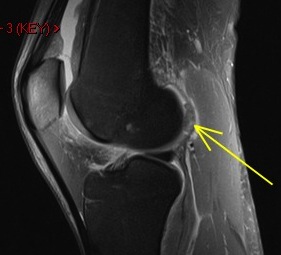

36 y/o was running and struck by car

Osteochondral fracture of the medial femoral trochlea. Notice the displaced chondral fragment behind the lateral femoral condyle interposed between the condyle and the posterior lateral capsule. Moral of the story – if you see an acute defect, look for the fragment.

Osteochondral fracture femur with displaced fragment